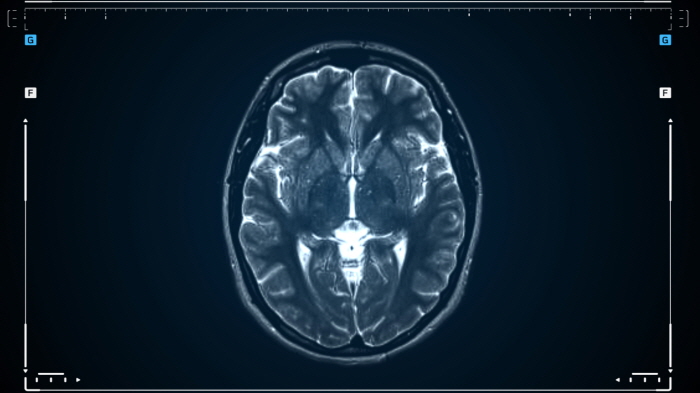

이 질환은 발작, 두통, 인지 기능 저하, 뇌수종 등 다양한 증상을 유발하며, 진단을 위해 MRI, CT 촬영 및 혈액 검사가 필요합니다.

ㆍ MRI(자기공명영상): 뇌 속 유충의 위치와 크기를 정확히 확인할 수 있습니다.

ㆍ CT(컴퓨터 단층촬영): 유충에 의해 뇌에 생긴 병변을 확인합니다.